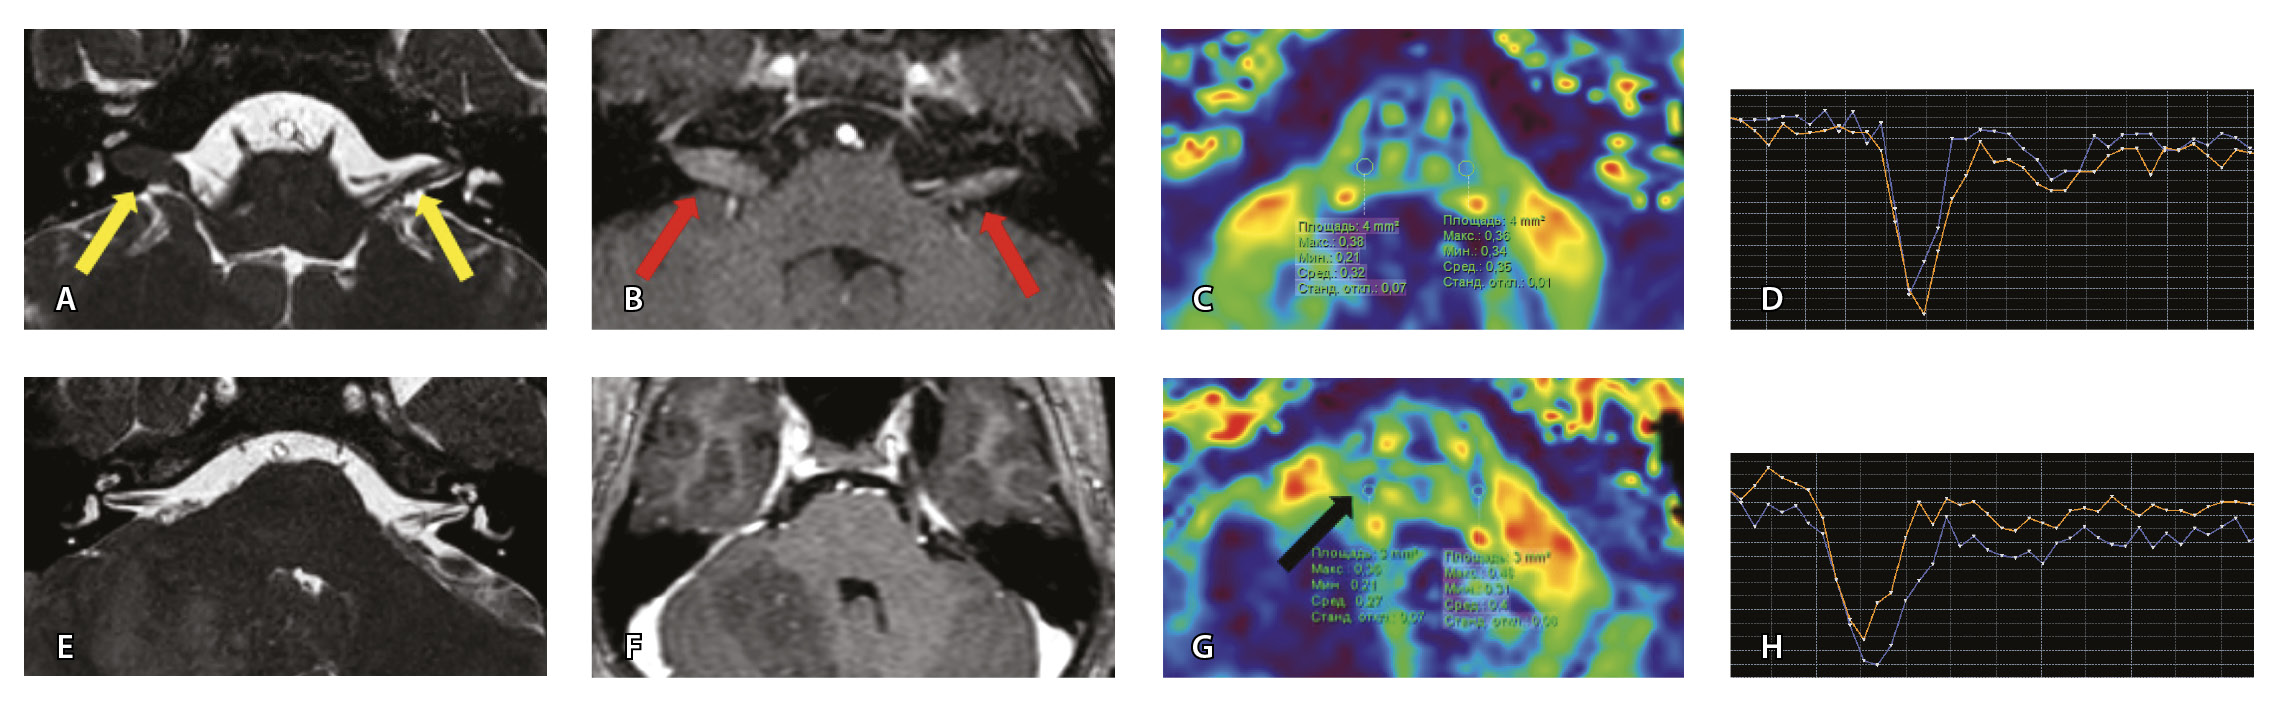

Проведена МП-МРТ головного мозга и черепно-мозговых нервов. Заключение: МР-признаки локального участка повышенного накопления контрастного вещества правым ЛН во внутреннем слуховом проходе – изменения могут соответствовать невриту ЛН (рис. 6).

Рис. 6. Пациентка З. Магнитно-резонансная томография (МРТ) головного мозга: А – прицельная T2-SSFP на область мосто-мозжечкового угла; Б – Т1-взвешенное изображение с контрастным усилением; В – диффузионно-тензорная МРТ (фракционная анизотропия, ФА); Г – Т2*-перфузия. На изображении T2-SSFP патологические изменения на уровне прохождения лицевых нервов во внутренних слуховых проходах не определяются (А). При контрастировании отмечается накопление контрастного вещества правым лицевым нервом во внутреннем слуховом проходе (Б, красная стрелка). На уровне моторных ядер лицевого нерва в заднем отделе варолиевого моста на изображениях ФА на стороне поражения отмечается минимальное уменьшение показателя ФА до 0,33 (В, черная стрелка) и признаки гипоперфузии справа (Г, оранжевый график) по сравнению с контралатеральной стороной (Г, синий график). Данный пример демонстрирует типичные изменения при мультипараметрической МРТ у пациента с параличом Белла